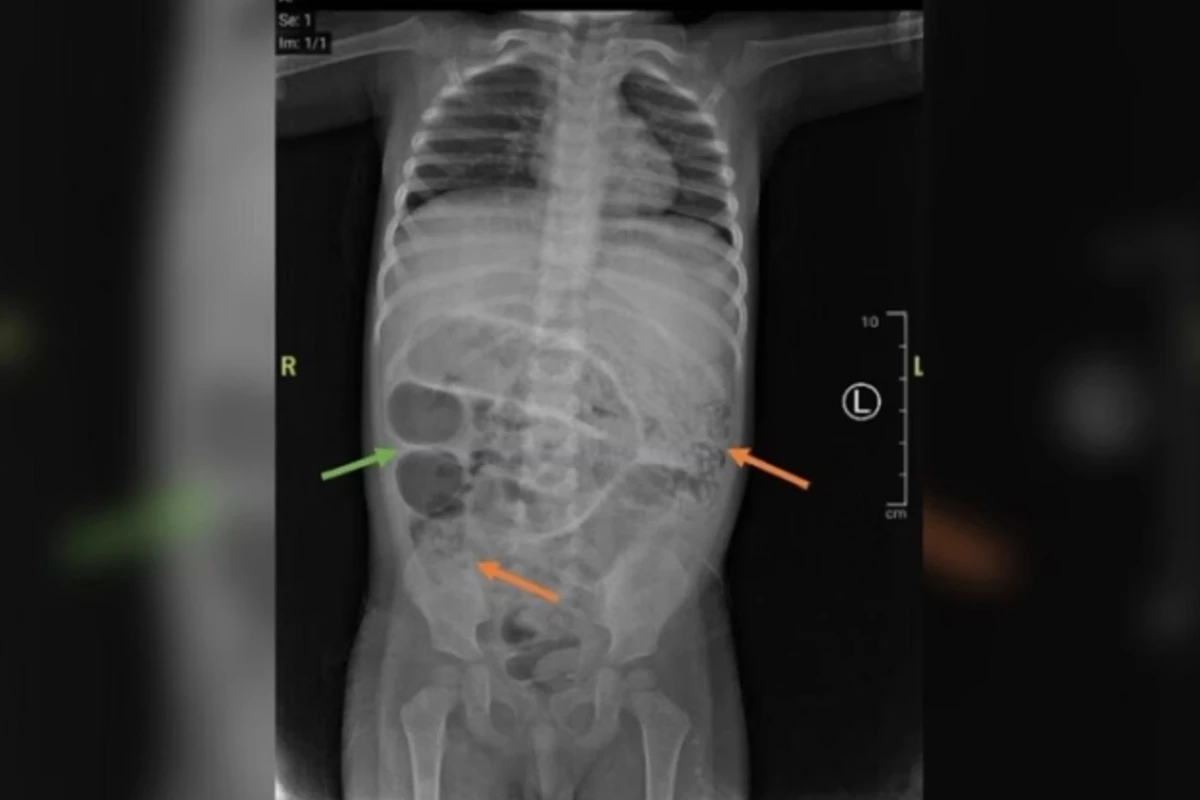

Um recém-nascido precisou ser submetido a um procedimento cirúrgico para remover dois embriões no abdômen.